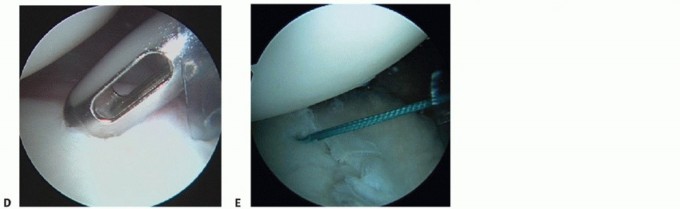

This is a critical step so that a freely mobile labrum can be placed up on the glenoid, thereby restoring its bumper effect. Anchor placement begins at the most inferior aspect of the glenoid, usually the 5:30 or 6:30 position, depending on the side involved (TECH FIG 1D).

TECH FIG 1 • A. Probe entering the posterior cannula is demonstrating mobility of posterior Bankart lesion with evidence of granulation tissue in the defect. B. After the lesion is defined, a Liberator knife is introduced to take down the fibrous interface in the posterior Bankart lesion. C. After preparation using a high-speed burr, the posterior inferior aspect of the glenoid is lightly decorticated in preparation for anchor placement. D. Initial anchor placement begins at the inferior extent of the glenoid with the use of a guide. E. First anchor in place 2 mm up on the articular surface.

This position allows secure placement of an anchor while allowing optimal inferior capsular plication. Bioabsorbable anchors are employed for this reconstruction (TECH FIG 1E).

A Spectrum 45-degree-offset suture passer, preloaded with a no. 0 polydioxanone (PDS) monofilament suture (Ethicon, Somerville, NJ), is passed through the posterior cannula, capturing the inferior capsule in the area of the posterior band of the IGHL (TECH FIG 2A).

TECH FIG 2 • A. The Spectrum suture passer is used to capture inferior capsular tissue and the posterior band of the IGHL. B. After anchor placement, stability is assessed with gentle traction on the anchor sutures and a monofilament suture is passed through the suture passer. (continued)

The PDS suture is reeled into the joint through the passer and retrieved in the posterior cannula using a ring grasper (TECH FIG 2B,C).

The deep limb of the PDS is tied to one limb of the anchor suture, and using a pulling technique, the PDS is drawn in a retrograde fashion, with the anchor suture attached, through the capsule and labral tissue, thereby creating a simple stitch (TECH FIG 2D*).

This allows the inferior capsule to be drawn superiorly and medially while at the same time closing the posterior Bankart lesion.